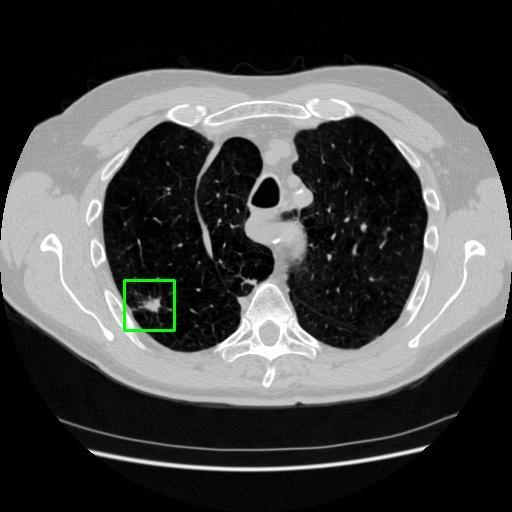

We developed an AI-based system using deep learning models for analyzing lung CT scans to detect and classify pulmonary nodules. We chose the YOLOv11 architecture for its enhanced object detection capability and adapted it specifically for medical imaging, incorporating pixel-level precision and severity classification.

Classification into three severity levels with colored bounding boxes.

Successfully built and deployed an AI model (YOLOv11) capable of detecting lung nodules in CT scans with high accuracy and real-time performance.

Designed a severity classification system that categorizes nodules into null, moderate, and severe using colored bounding boxes, assisting in rapid clinical decision-making.